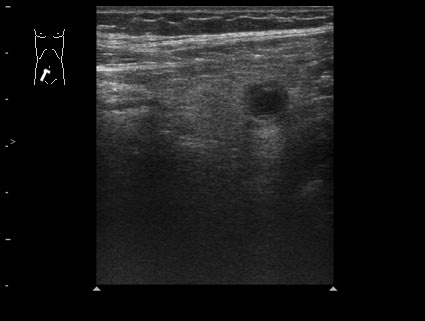

Пациент 32 лет.

В правой подвздошной области определяется утолщенный аппендикс, не компрессируется при надавливании датчиком, в просвете определяется аппендиколит; окружающие аппендикс ткани инфильтрированы.